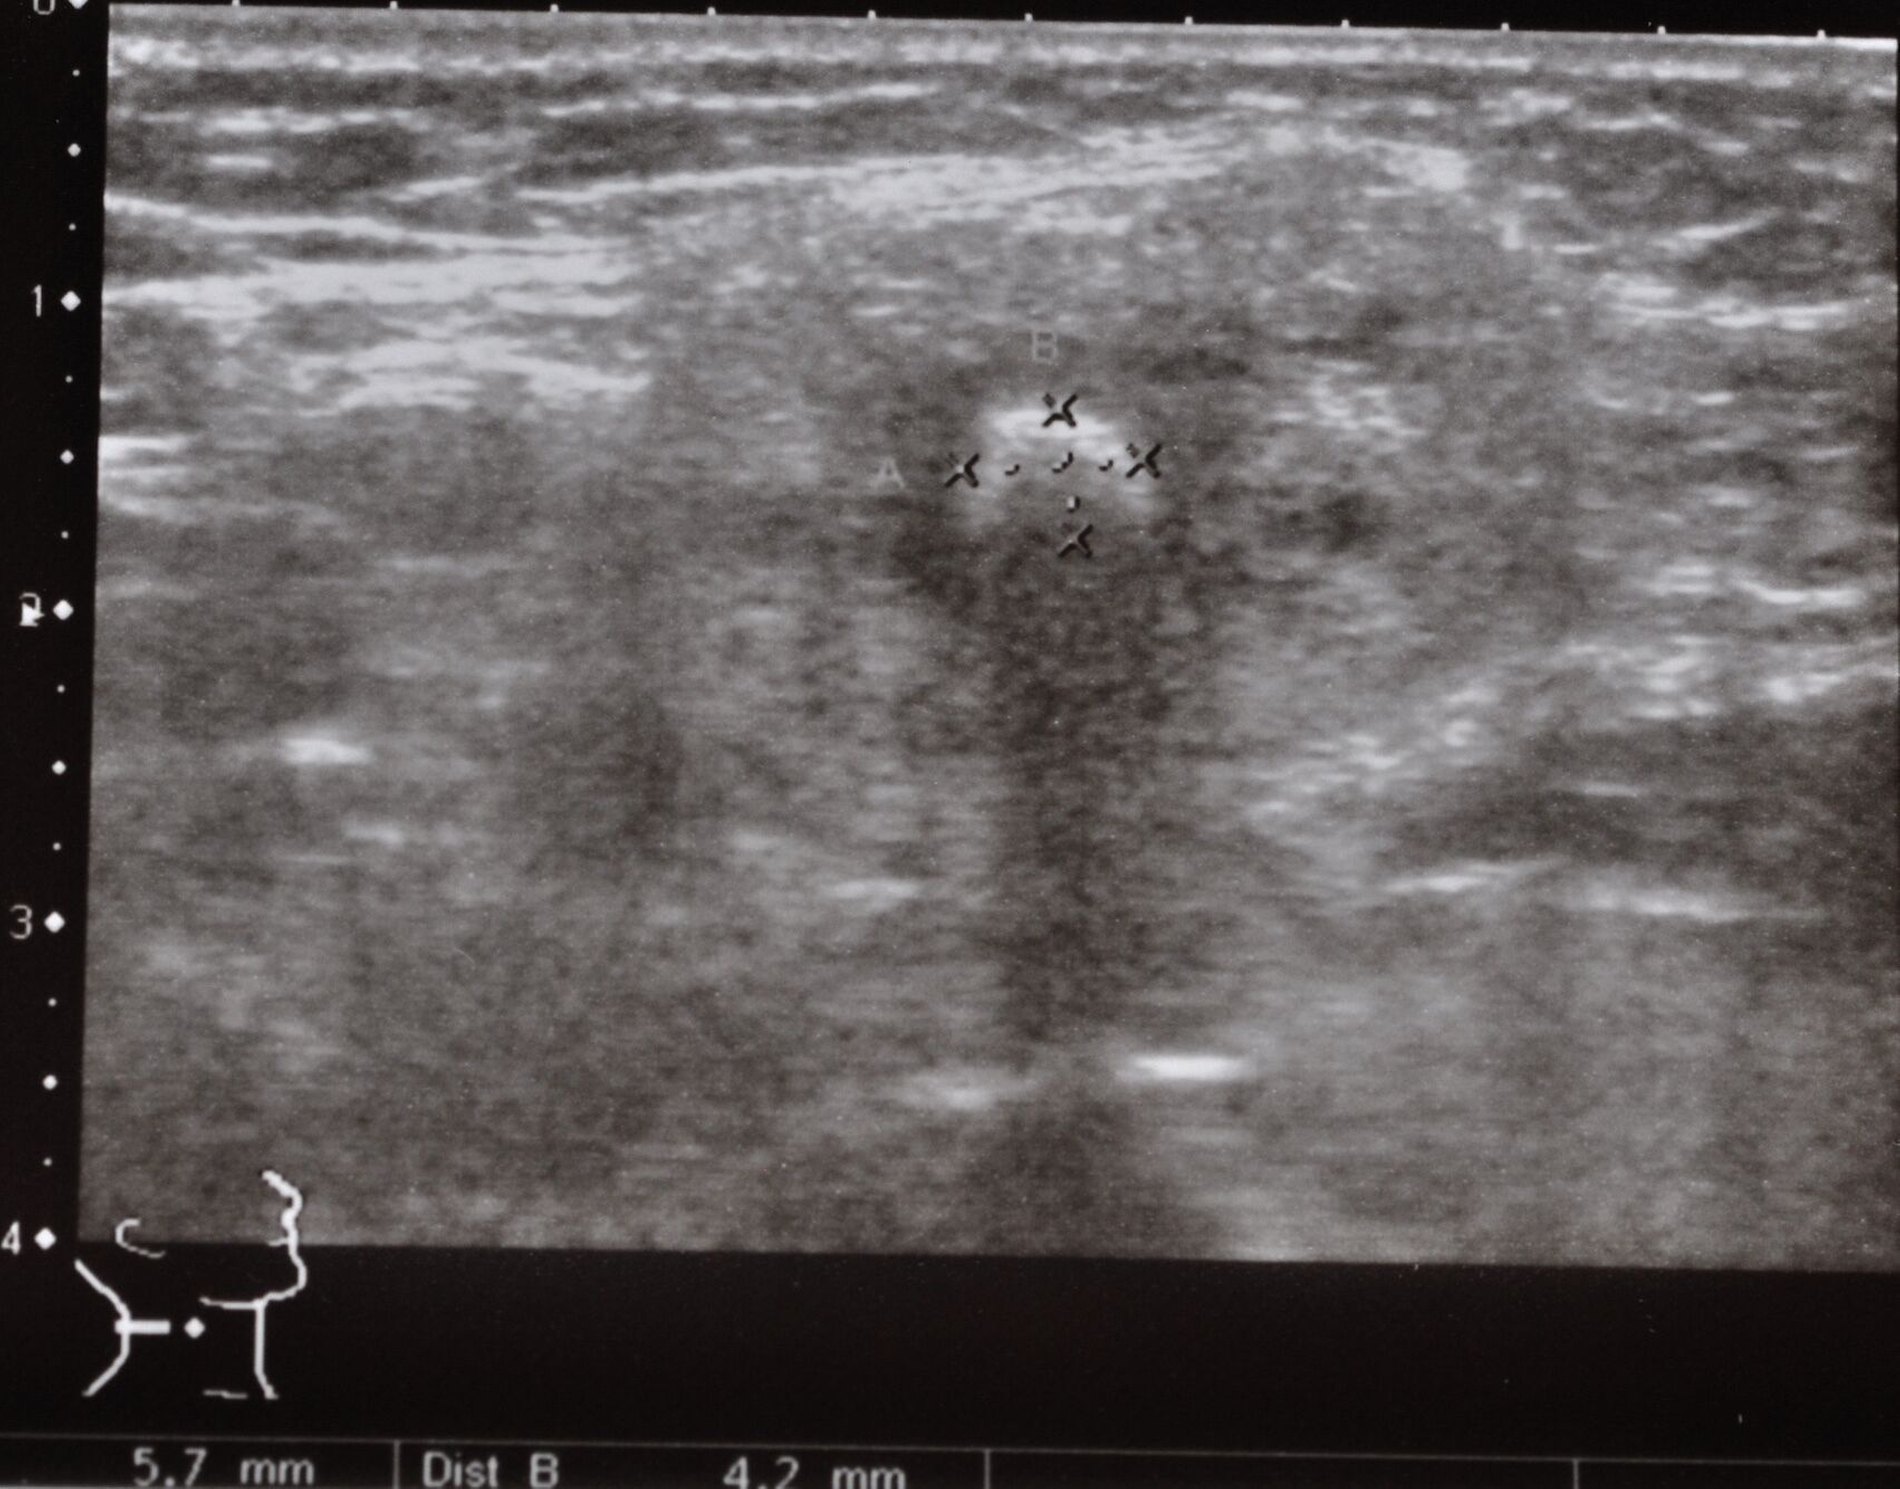

Nach diesem Eingriff habe sich ihr Zustand vorübergehend verbessert, jedoch seien die Beschwerden in den vergangenen Wochen wieder intensiver geworden. Bei der klinischen Untersuchung zeigte sich eine druckempfindliche Schwellung im kaudalen Bereich des rechten Unterkiefers (Abbildung 1). Speichel konnte aus dem ipsilateralen Ausführungsgang der Glandula submandibularis nicht exprimiert werden. Die darauf folgende Sonografie bestätigte den Verdacht auf das Vorhandensein eines Sialolithen im proximalen Ausführungsgang der rechten Glandula submandibularis (Abbildung 2).

Nach der deutschen S2k-Leitlinie „Obstruktive Sialadenitis“ (AWMF-Register-Nr. 017-025) sollte die initiale Anamnese vor allem die Art, Intensität und Häufigkeit der Beschwerden sowie potenzielle Komplikationen erheben. In der anschließenden klinischen Untersuchung empfehlen die Autoren der Leitlinie primär eine Inspektion und bimanuelle Palpation von Drüsen und Ausführungsgängen, eine Beurteilung des Speichels und ein Ausstreichen der betroffenen Drüse. Die Sonografie als nicht-invasive und kostengünstige bildgebende Technik sollte zur Untersuchung von Speicheldrüsenerkrankungen als das diagnostisch bildgebende Verfahren der ersten Wahl eingesetzt werden; die Sensitivität zur Erkennung von Speichelsteinen wird mit bis zu 95 Prozent beziffert [Goncalves et al., 2017]. Fortschritte in diagnostischen Modalitäten wie CT und MRT haben den diagnostischen Prozess revolutioniert, wobei die S2k-Leitlinie eine individuelle Auswahl einer eventuell weiter notwendigen Diagnostik angibt. Auch die Sialendoskopie kann – wenn notwendig – potenzielle Gangverengungen oder andere Hindernisse identifizieren und simultan eine Intervention ermöglichen.

Die Sonografie bleibt das bildgebende Verfahren der ersten Wahl zur Detektion von Speichelsteinen aufgrund ihrer hohen Sensitivität und ihrer Nichtinvasivität.